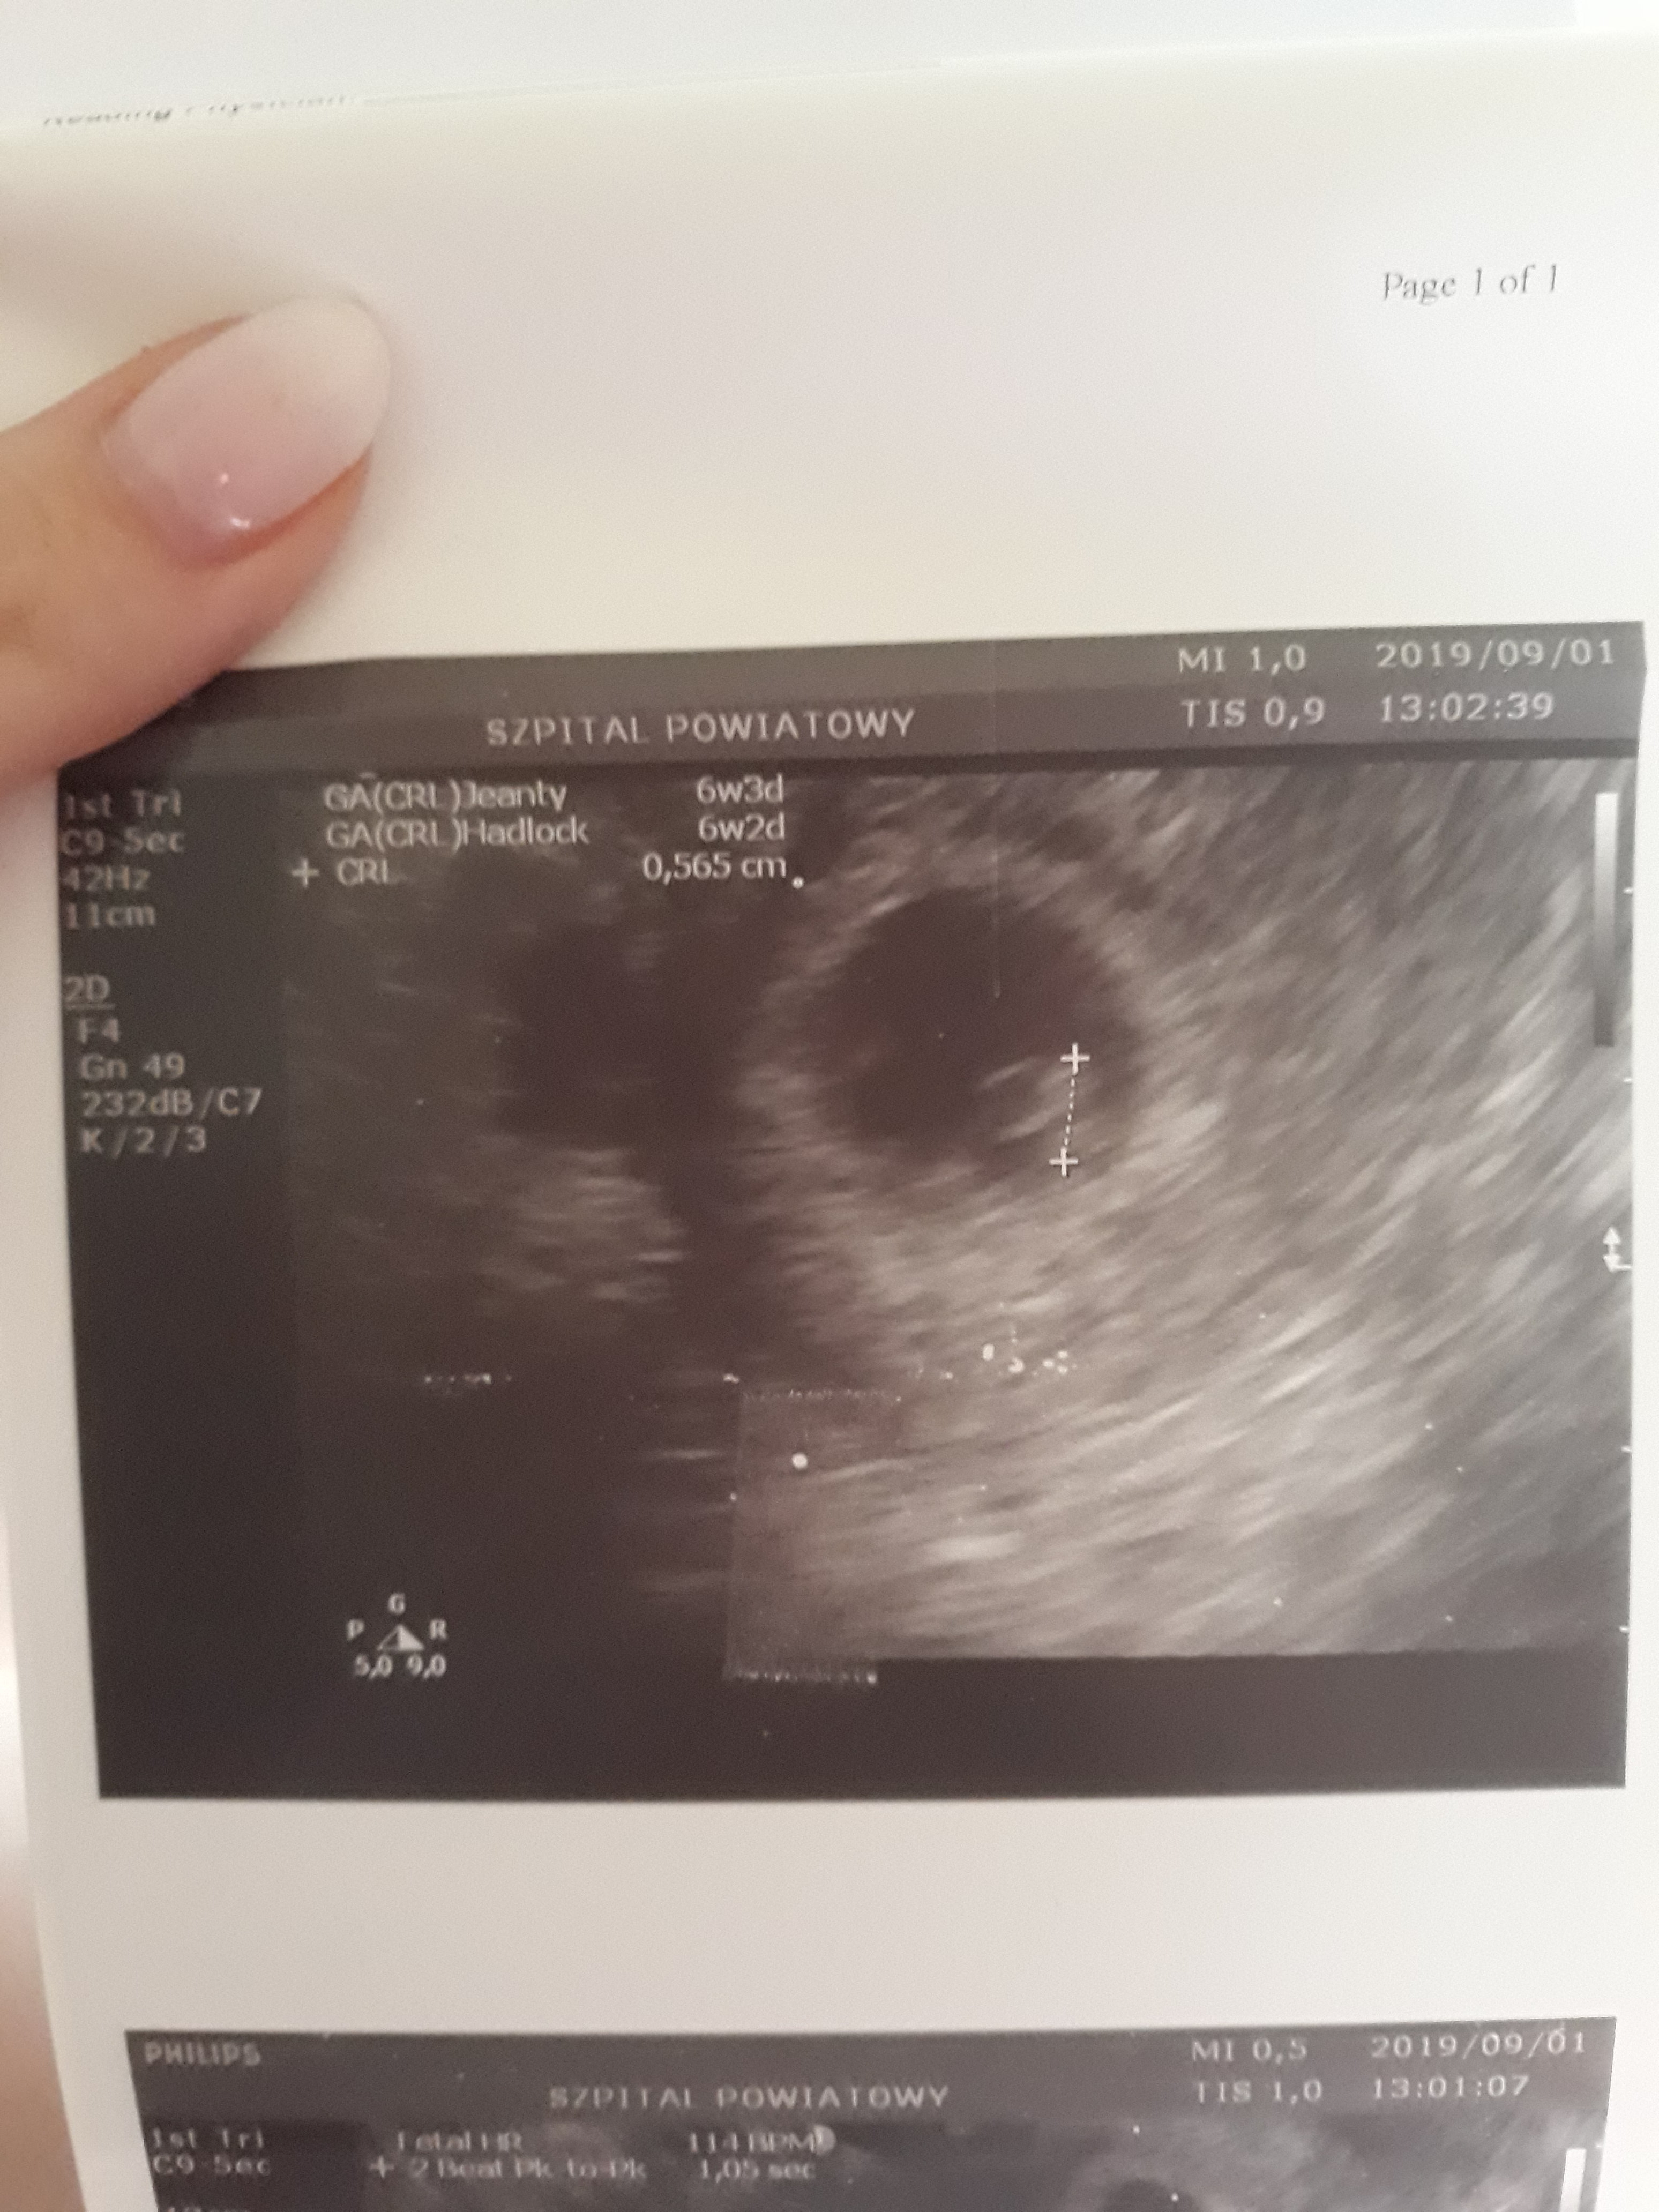

Tak szybko kolejne?Jestem już po usg. Całe 0.565 cm malusiego człowieczka z bijącym pięknie serduszkiem 114 BPM.

Żadnych krwiaków... musi być już tylko dobrze. Kolejne USG w piątek. Zobacz załącznik 1017069Zobacz załącznik 1017068